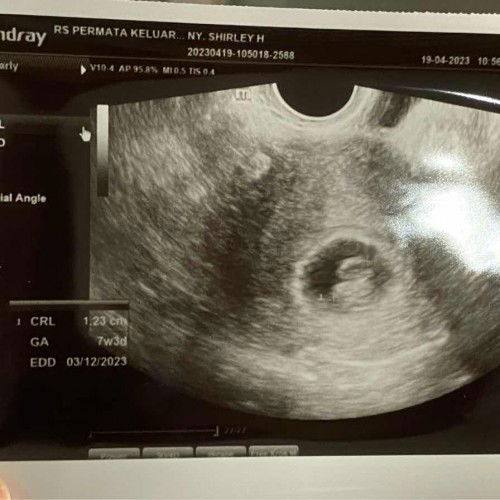

Halo bunda2 yg hebat dan kuat. Aku mah share pengalaman aja. Aku punya riwayat keguguran tahun lalu. Skrng di kehamilan kedua, hr sabtu pagi lalu aku ada flek lgsg warna merah, adanya kalau di lap tissue, gak netes di CD. Aku lgsg USG transV. Hasilnya DJJ bagus, ukuran bagus. Aku lgsg bedrest total. Makan minum mandi keramas di kasur. Jalan cuma ke toilet itupun jalannya pelaaaaan banget. Minggunya msh ngeflek warna coklat sdkt (dan jarang), senin hilang total, eeehh selasa ada lagi (sdkt tp cukup sering), nah rabu td pagi flek coklat tp agak banyak (sekitar 5cm), aku was2 lalu lgsg cek USG, puji Tuhan DJJ makin kenceng, ukuran normal. Jd mom, aku tau kita kehamilannya msh muda, mgkn banyak jg yg ngalamin flek. Tp jgn parno dan takut. Jangan mikir kalo flek pasti gue keguguran. JANGAN!! Kuncinya adalah bedrest total dan pikiran yg relax. Udah itu aja. Cemas pasti ada tp cukup bbrp detik dan menit aja. Krn kalau maminya happy, janinnya happy😊 Hati yg gembira adalah obat. Percaya dan imani kita sehat, janin sehat. Sisanya kita berserah sama Tuhan. Kalau Tuhan dah kasih, siapapun dan apapun gak jadi penghalang. Yg penting tenang dan usaha. Semoga jd kekuatan buat semuanya. Semoga kita dan kehamilan kita selalu sehat sampai persalinan. Aminnn… Semangat para bunda😊😊